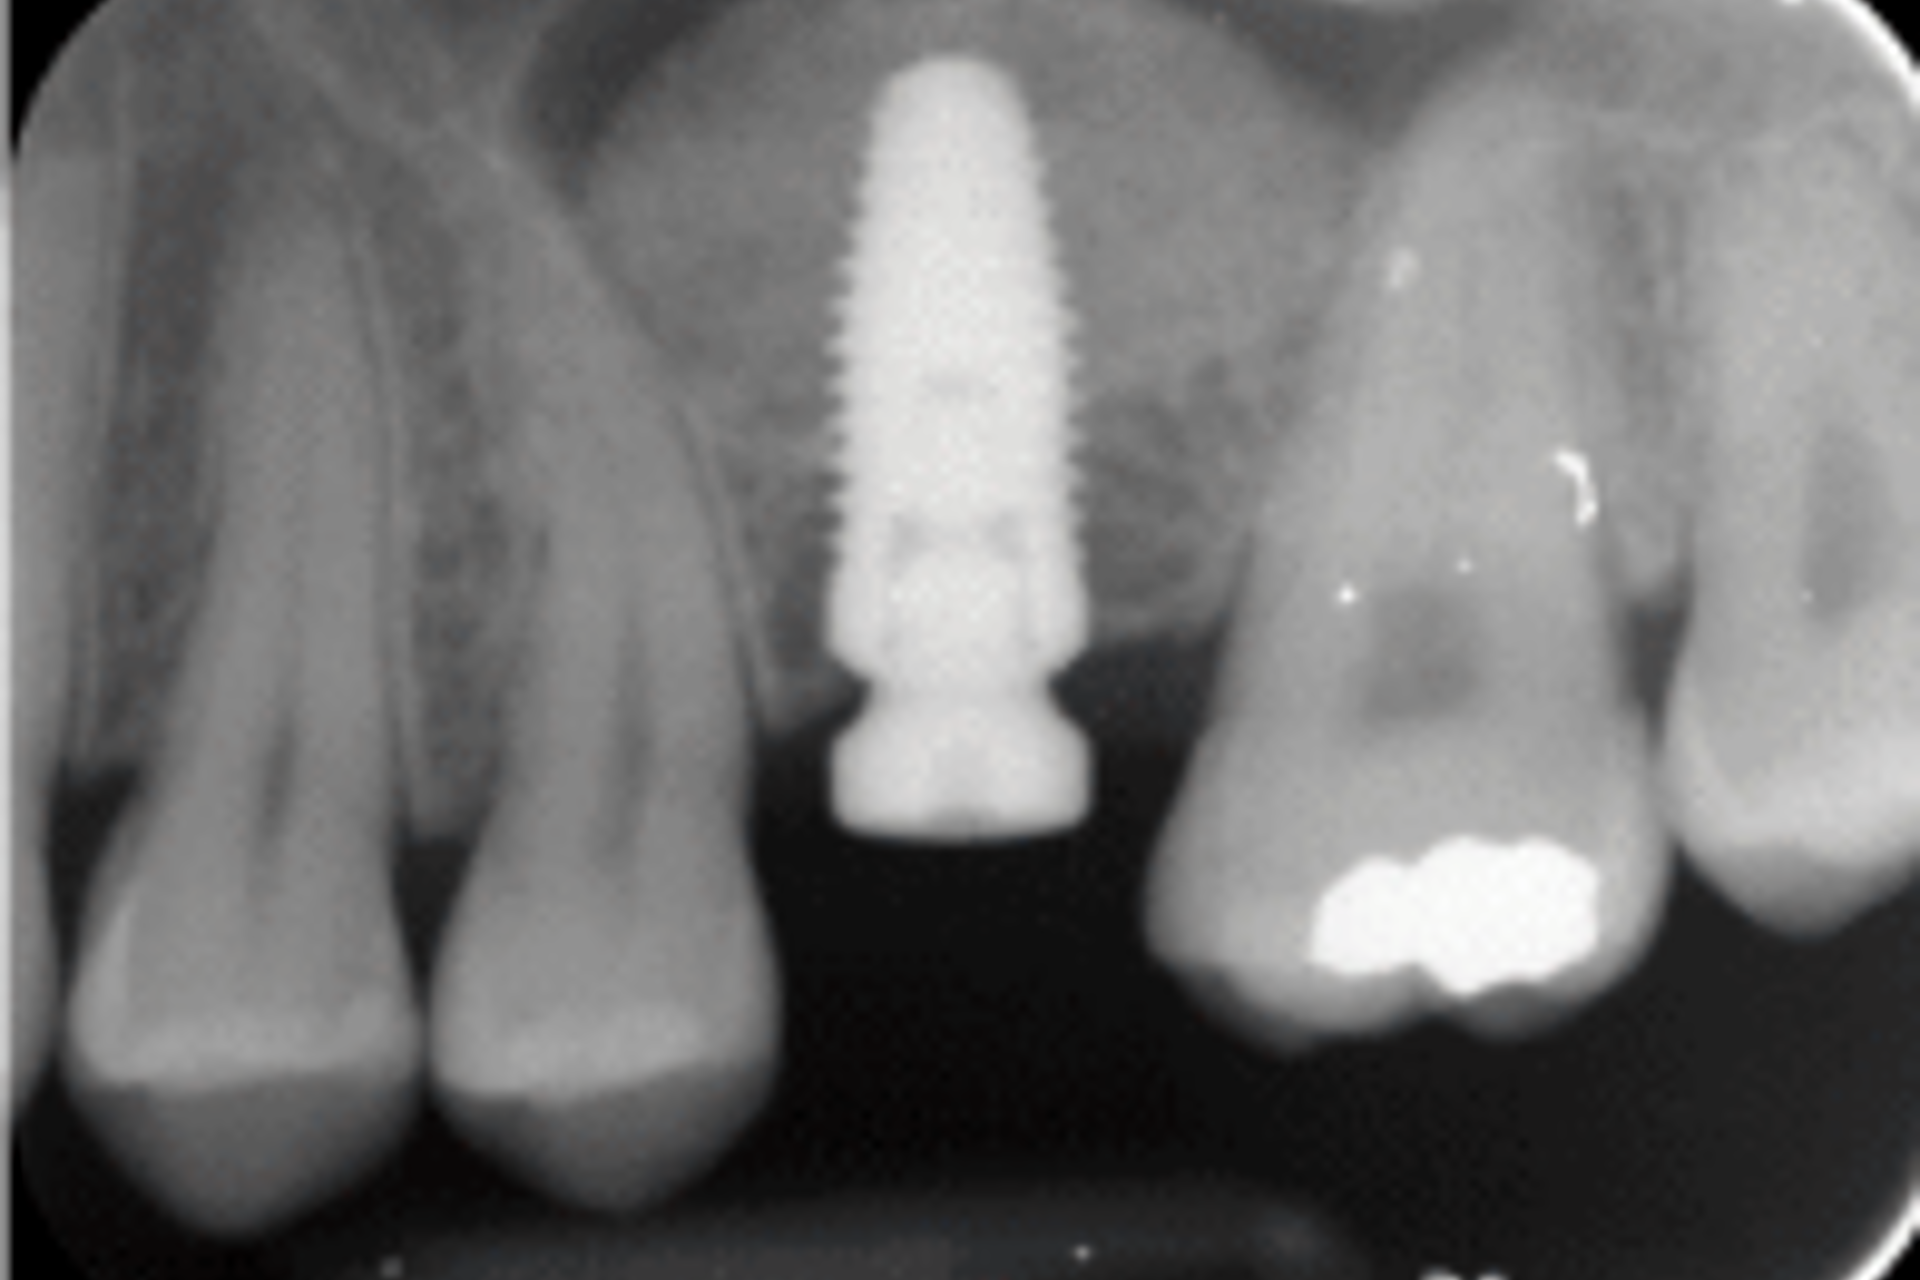

Bone regeneration around dental implants is achieved by grafting bone. Most commonly bone grafting is required when a patient does not have enough healthy natural bone at the dental implant site to support a dental implant. (Figures 15 A, B & C).

Image below shows implant placement with sinus lift and use of bone graft.